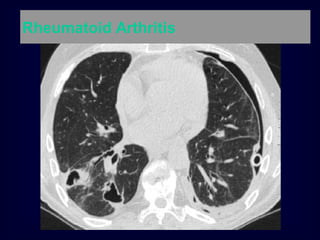

Pulmonary fibrosis and rheumatoid arthritis.

Pulmonary fibrosis andrheumatoid arthritis.